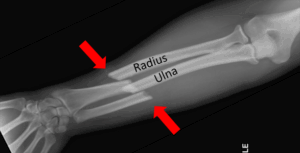

The forearm is the distal portion of the upper extremity between the wrist and the elbow. Two long bones, the radius and the ulna, run parallel between those two joints and are connected by a fibrous membrane. Based on the way the bones are connected, they allow for rotation of the forearm (pronation and supination):

A forearm fracture may involve the radius, the ulna, or both. A distal radius or ulnar fracture is often referred to as a wrist fracture when the broken portion is close to that joint, as with the injury that Aaron Rodgers had. A break in the middle portion of the bones in adults requires such a strong force that both bones are often involved. This was the case in 2014 for CB Ike Taylor, who sustained a fracture of both bones of his right forearm, resulting in obvious deformity.

Other than minimal hairline fractures, plain X-ray can make the diagnosis, and an MRI is not necessary. Here is an example:

www.radiopaedia.org